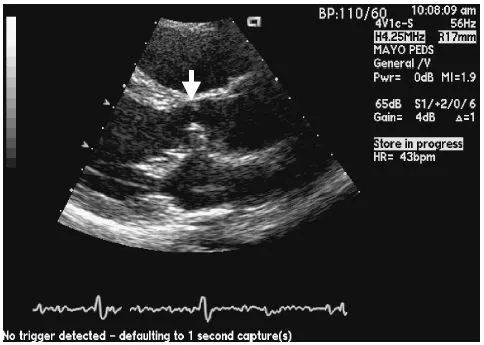

A 17-year-old girl born with partial atrioventricular septal defect (AVSD) had closure of the primum atrial septal defect (ASD) and repair of a cleft in the anterior leaflet of the mitral valve when she was 18 months of age. She did well and her growth and development were normal. She participated in high school sports and had no limitations. It was noted several years prior to the current presentation that she had developed a systolic ejection murmur. Echocardiography demonstrated the images shown in Fig. 2.1. That echocardiogram also demonstrated trivial mitral valve regurgitation and mild aortic valve regurgitation.

The echocardiograph in Fig. 2.1 demonstrates tissue in the left ventricular outflow tract (LVOT) that represents accessory connections from the anterior leaflet of the mitral valve to the septum.

Fig. 2.1 Parasternal long axis projection demonstrating a subaortic membrane (arrow) that developed in a teenager, 15 years after repair of partial AVSD.